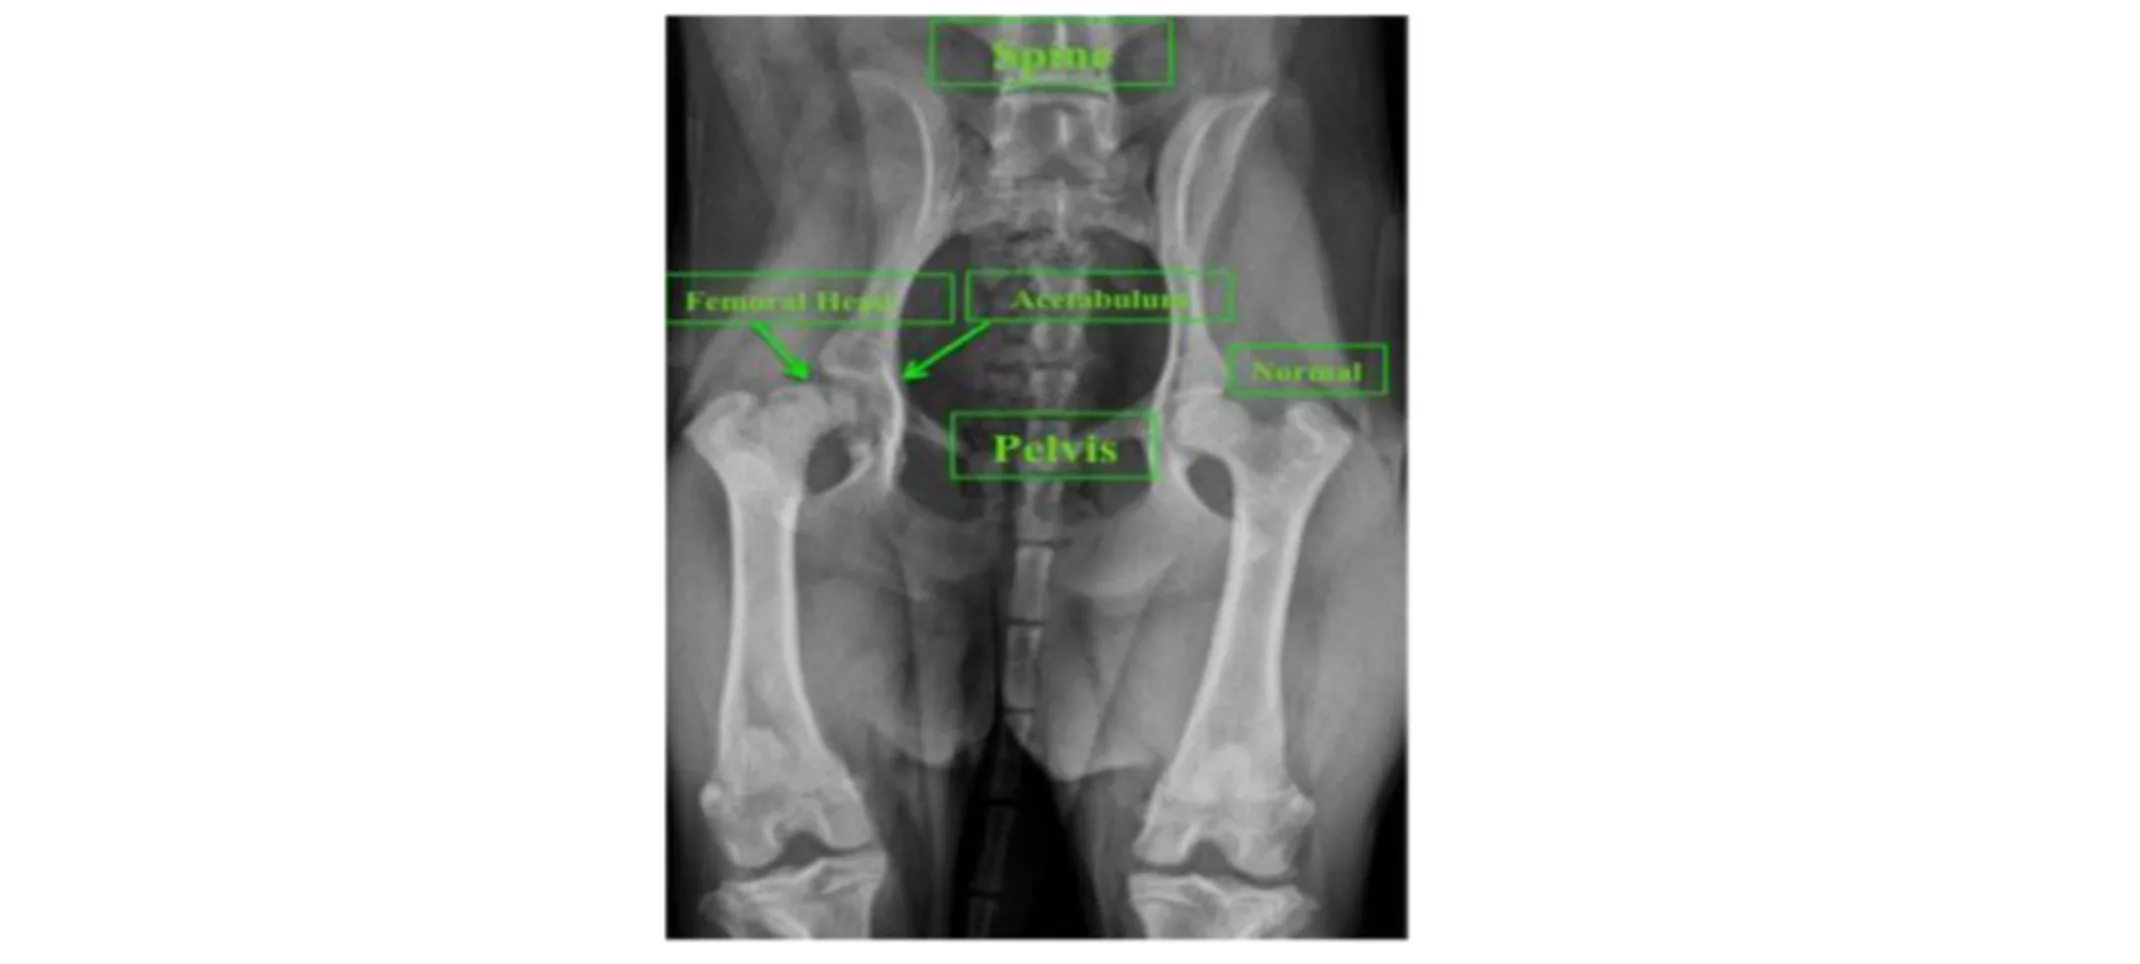

Diagnostic imaging such as radiography (X-rays) or CT may be used to determine the underlying cause of hip pain/lameness and potentially plan for surgical procedures that preserve the hip joint. The choice to perform an FHO is determined by the patient’s condition and discussion between the owner and veterinarian. Below is a radiograph of a patient suspected to have aseptic necrosis of the femoral head. Notice the difference in density and appearance between the left and right femoral head. An FHO was chosen for this patient.